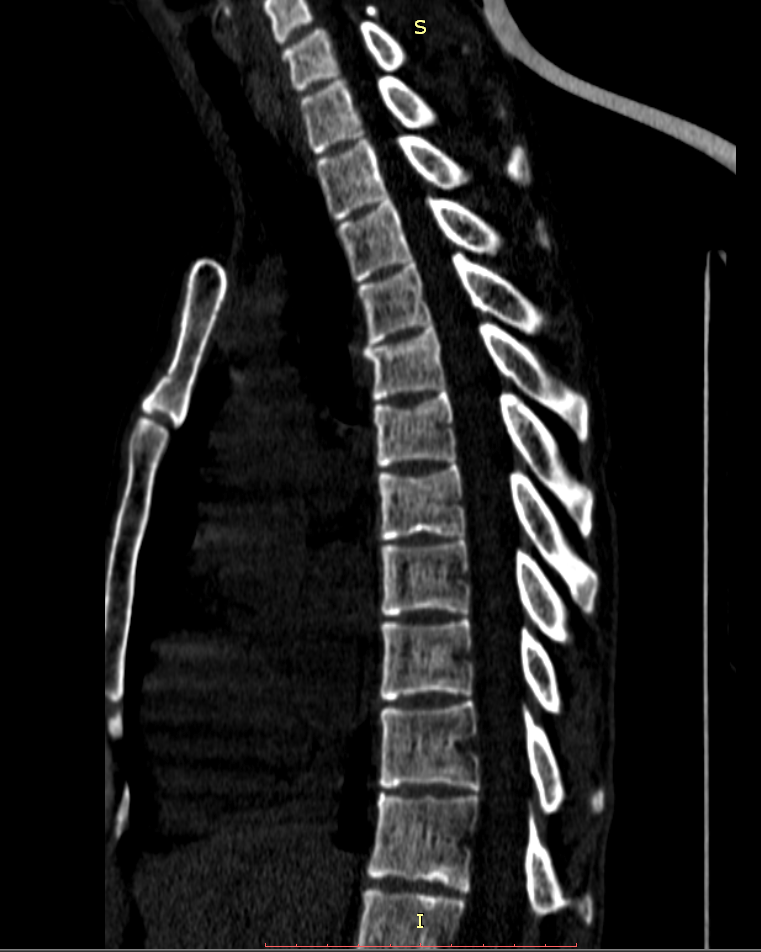

Здравствуйте! Меня сбил автомобиль. Бригада скорой помощи доставила меня в стационар с диагнозом - сотрясение мозга, ушиб грудного отдела позвоночника, компрессионный перелом грудного отдела позвоночника. При поступлении в стационар мне было сделано несколько рентгеновских снимков и поставлен диагноз - компрессионный перелом 4 грудного позвонка. Из-за "мутных" рентгеновских снимков через 9 дней мне сделали КТ и диагноз сняли на основании этого заключения.Судебная медицина - Прикрепленное изображение Мне сказали что перелом шейного позвонка у меня старый и поменяли диагноз - ушиб верхне-грудного отдела позвоночника, болевой синдром. По запросу я получила копию записи КТ. Всю запись КТ выложить не могу, т.к. не могу убрать фамилию. Выкладываю некоторые снимки: Судебная медицина - Прикрепленное изображение Судебная медицина - Прикрепленное изображение Судебная медицина - Прикрепленное изображение Судебная медицина - Прикрепленное изображение Судебная медицина - Прикрепленное изображение Судебная медицина - Прикрепленное изображение Судебная медицина - Прикрепленное изображение Действительно ли по этим снимкам можно сказать, что перелом шейного позвонка "старый"? Правильно ли описание КТ? Я не эксперт, но по-моему 5 грудной позвонок тоже поврежден. Можно ли оспорить заключение врача делавшего КТ? Если можно, то как это сделать? Ведь речь идет об установлении причинно-следственной связи между ДТП и травмой, а до ДТП у меня никаких травм позвоночника не было. Может рентгеновские снимки тоже о чем то скажут.Судебная медицина - Прикрепленное изображениеСудебная медицина - Прикрепленное изображениеСудебная медицина - Прикрепленное изображение

Для этого надо исследовать все сканы. Желательно - с 3D-реформацией изображения. С внимательным анализом костной структуры на уровне дефекта (есть ли признаки отека костной ткани в его зоне, наличие реакции мягких тканей, состояние краев фрагментов и т.д.). Получите все сканы КТ на диске или на флешке (они должны храниться в архиве КТ). И проконсультируйте их у высококвалифицированного специалиста по КТ и/или в любом крупном Бюро судебно-медицинской экспертизе, в штате которого есть эксперт-рентгенолог. Возможно, понадобится сделать контрольное КТ исследование с целью обнаружения динамики выявленных изменений (впрочем, вопрос об этом будет решен после ознакомления рентгенолога с КТ, т.к., возможно, доп.исследование не будет необходимо или же более целесообразным окажется иной вариант лучевой диагностики). По результатам консультации станет понятно, есть ли реальные основания для заявления мотивированного ходатайства о назначении дополнительной или повторной экспертизы (как это сделать - подскажет Ваш адвокат).